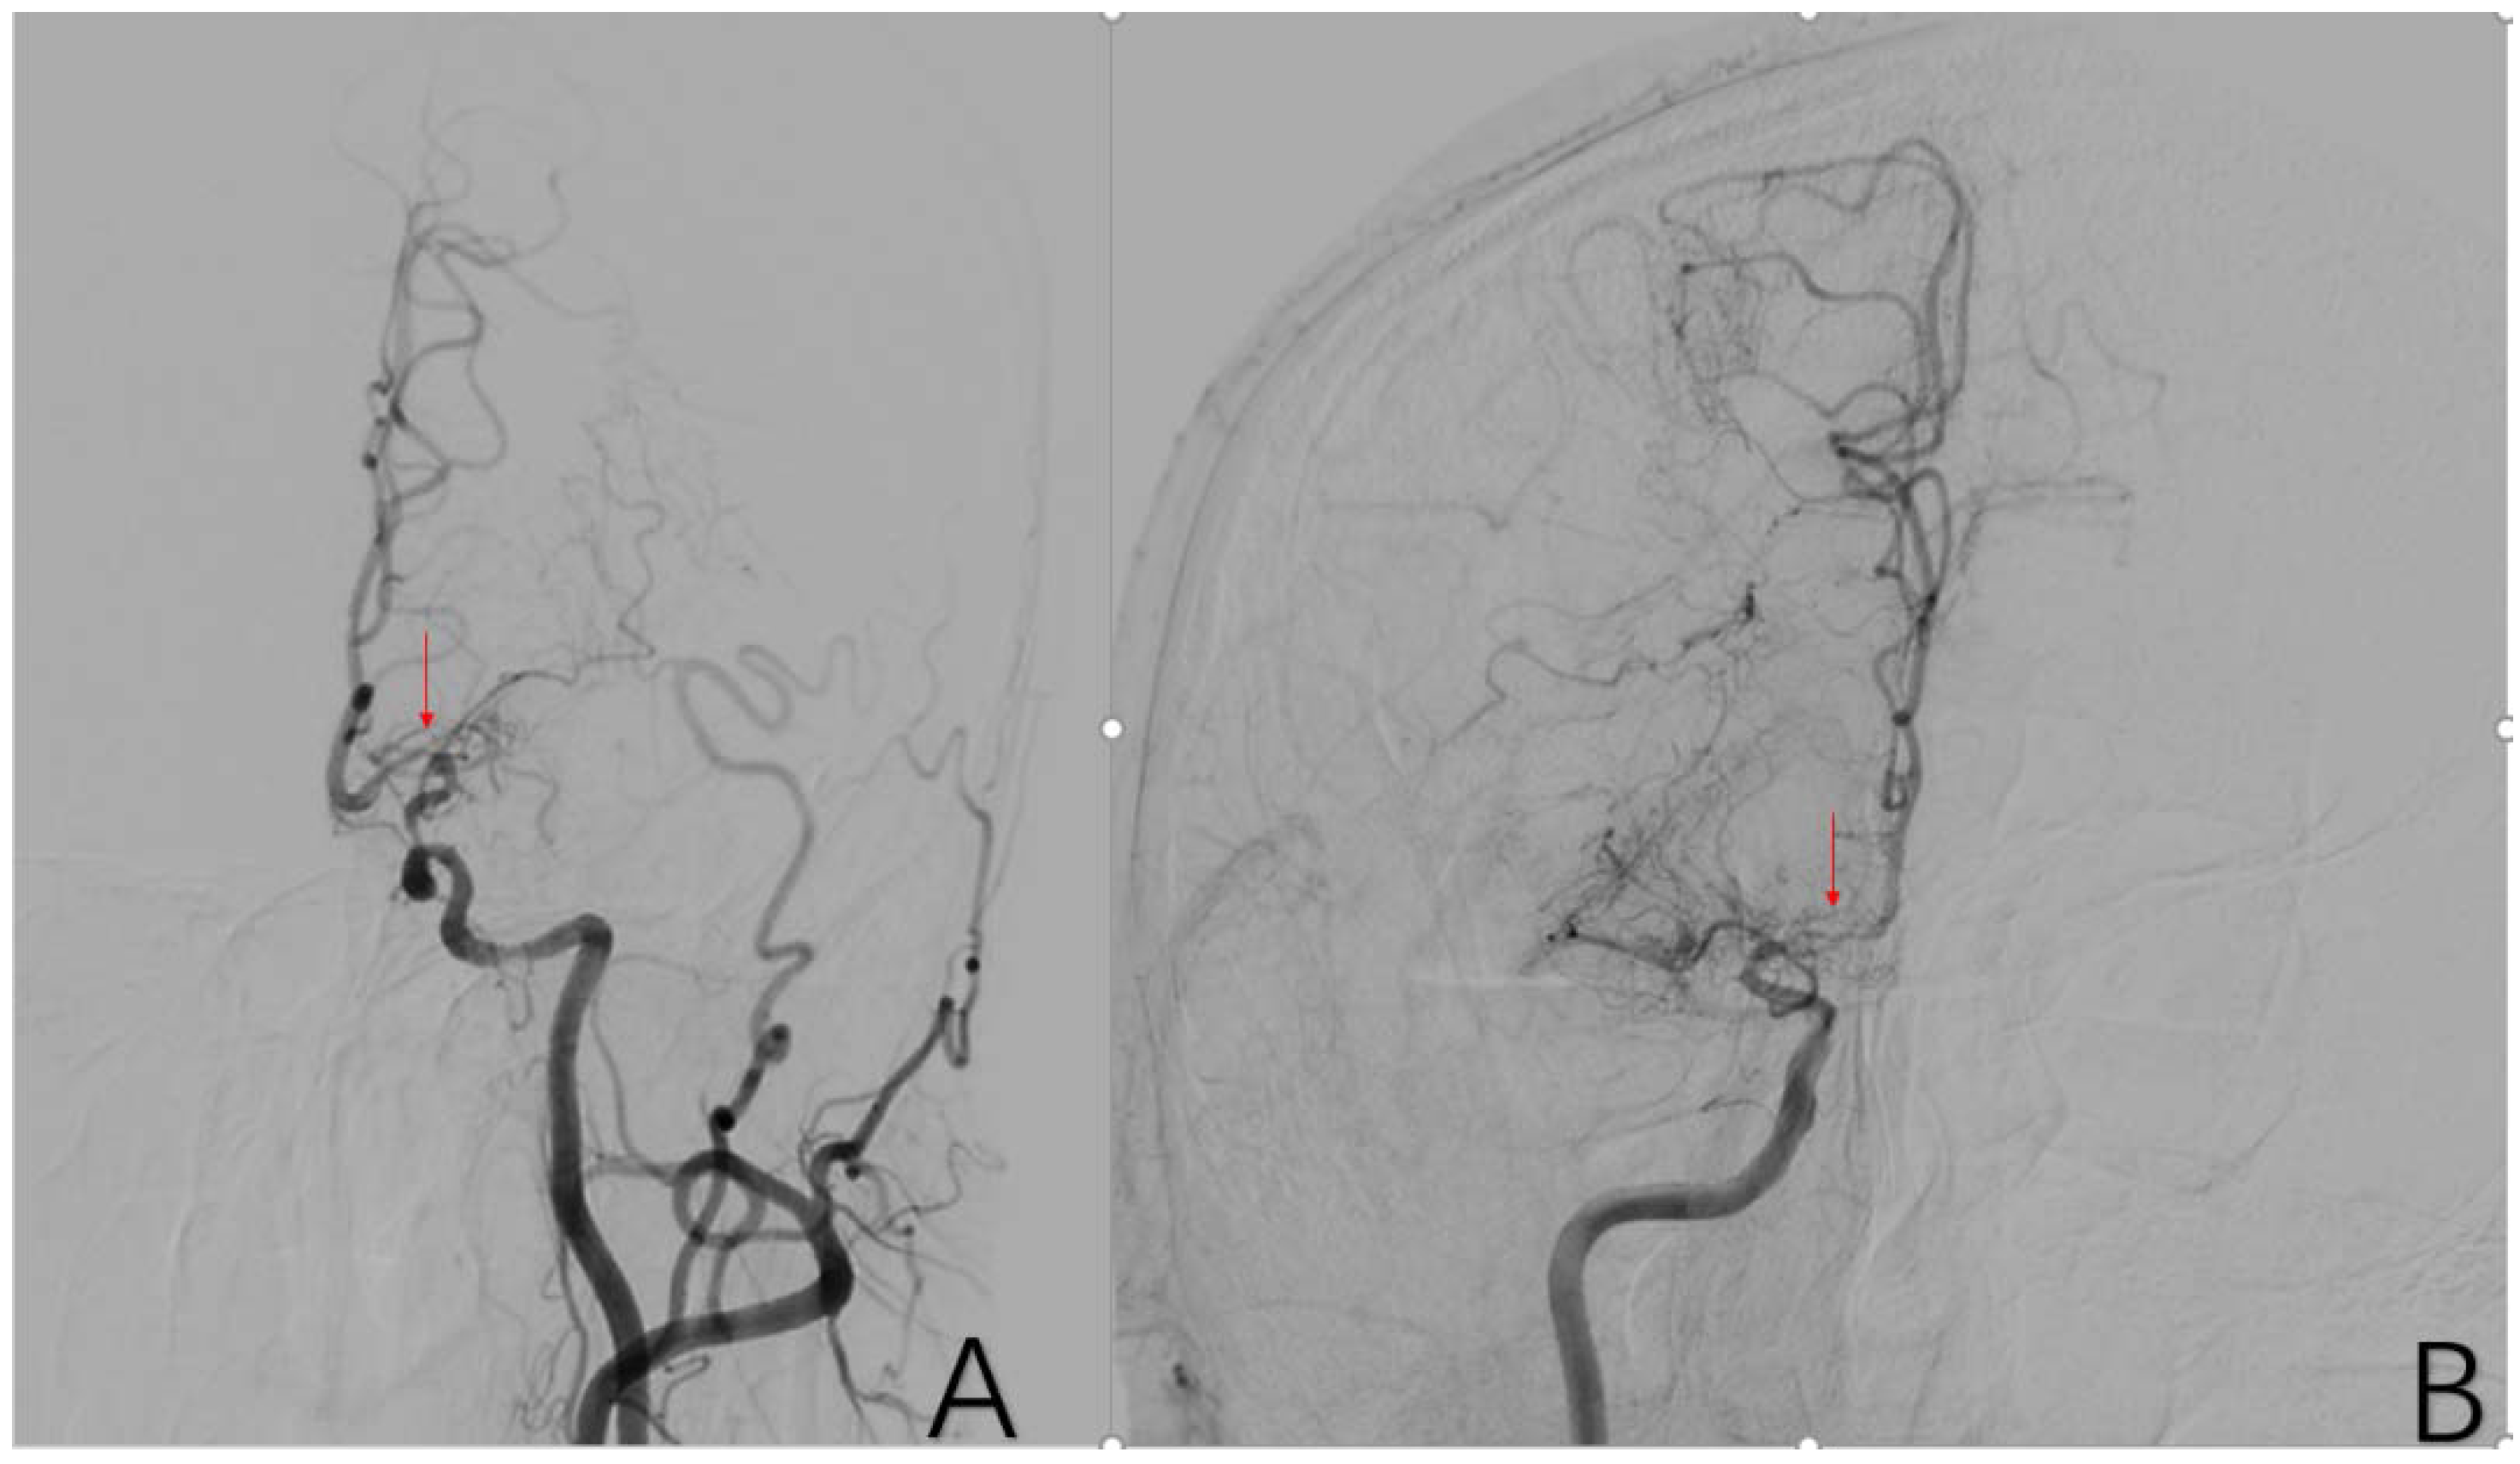

2.3.7. Factor 2 A1 Stenosis

2.3.8. Factor 3 M1 Stenosis

2.3.9. Factor 4 PCA Anomaly

2.3.10. Factor 5 Posterior Circulation Compensation

2.3.11. Factor 6 Unstable Compensation

2.3.12. Factor 7 Extracranial Arterial Compensation